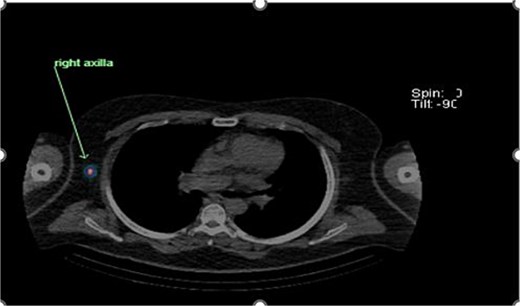

Preoperative lymphoscintigraphy was performed to detect the sentinel lymph node (Fig. 1), expecting it to be in the right inguinal region (Fig. 2). However, drainage to both the right axillary (Fig. 3) and inguinal areas was demonstrated. During surgery, a gamma camera confirmed drainage to both regions (Fig. 4). Blue dye was injected around the previous scar, and sentinel nodes were dissected guided by both blue dye and gamma camera for histopathology.

Unexpected drainage visualized toward the right axillary lymph nodes.

Intraoperative gamma probe confirming dual drainage to axillary and inguinal regions.